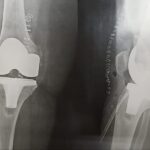

Your doctor will diagnose osteoarthritis based on the medical history, physical examination, and X-rays.

X-rays typically show a narrowing of the joint space in the arthritic knee.

The surgery is performed under spinal or general anesthesia. Your surgeon will make an incision in the skin over the affected knee to expose the knee joint. Then the damaged portions of the femur bone are cut at appropriate angles using specialized jigs. The femoral component is attached to the end of the femur with or without bone cement. The surgeon then cuts or shaves the damaged area of the tibia (shinbone) and the cartilage. This removes the deformed part of the bone and any bony growths, as well as creates a smooth surface on which the implants can be attached. Next, the tibial component is secured to the end of the bone with bone cement or screws. Your surgeon will place a plastic piece called an articular surface between the implants to provide a smooth gliding surface for movement. This plastic insert will support the body’s weight and allow the femur to move over the tibia, similar to the original meniscus cartilage. The femur and the tibia with the new components are then put together to form the new knee joint. To make sure the patella (knee cap) glides smoothly over the new artificial knee, its rear surface is also prepared to receive a plastic component. With all the new components in place, the knee joint is tested through its range of motion. The entire joint is then irrigated and cleaned with a sterile solution. The incision is carefully closed, drains are inserted and a sterile dressing is placed over the incision.